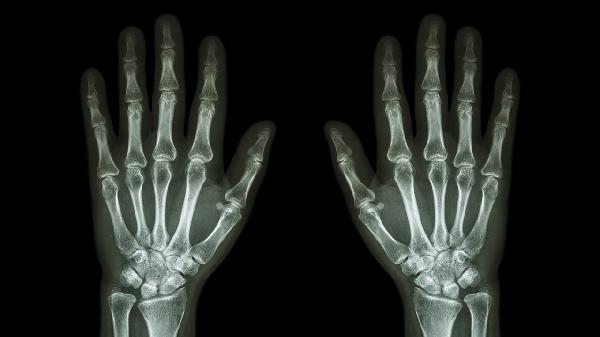

手指关节肿痛变形的原因有哪些

手指关节肿痛变形可能由骨关节炎、类风湿关节炎、痛风性关节炎、银屑病关节炎、外伤等因素引起。建议及时就医,明确病因后遵医嘱治疗。